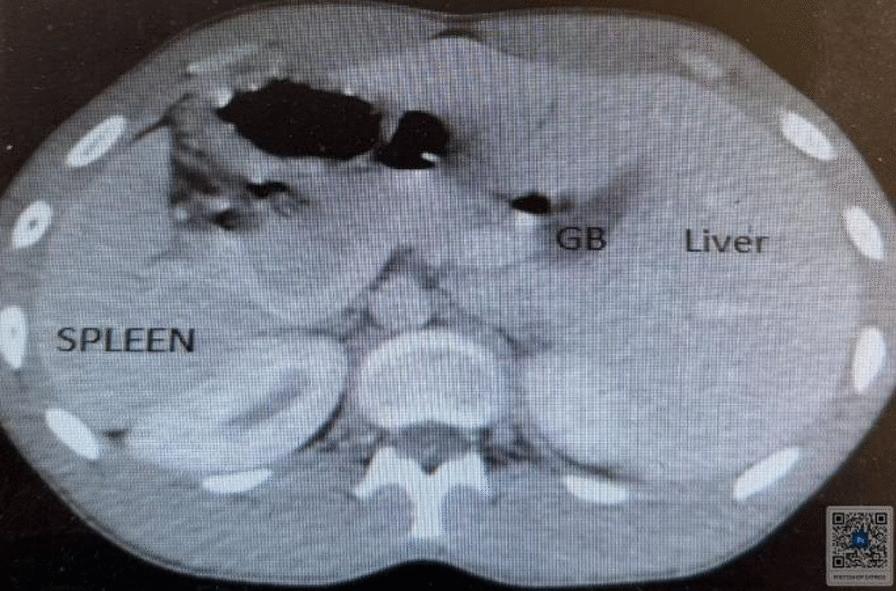

This case involved a 17-year-old Black African Semitic male patient who presented to our hospital with a complaint of intermittent productive cough, which started when he was 5 years old. He had a history of repeated treatment for lower respiratory tract infection and chronic sinusitis with frequent exacerbation. On examination, he had coarse crackles over the left posterior lower lung field. Heart sounds were appreciated on the right side. During imaging investigations, his chest X-ray posterior-anterior view showed dextrocardia and right side gastric shadow with left paracardiac bronchiectatic changes. A high-resolution chest computed tomography scan was suggestive of complete situs inversus. There were left lower lobe bronchiectatic changes. An electrocardiogram showed features of dextrocardia. Routine laboratory tests were within normal range. He was treated with thoracic physiotherapy, azithromycin 500 mg three times per week, and mucolytics, with no apparent exacerbations in the last 6 months.

该病例涉及一名17岁的黑非洲闪米特男性患者,他因间歇性咳痰前来我院就诊,这种情况始于他5岁时。他有下呼吸道感染和慢性鼻窦炎反复治疗史,且频繁加重。检查时,左后下肺野可闻及粗湿啰音。心脏听诊在右侧。影像学检查中,他的胸部后前位X线片显示右位心和右侧胃泡影,伴有左心旁支气管扩张改变。高分辨率胸部计算机断层扫描提示完全性内脏转位。有左下叶支气管扩张改变。心电图显示右位心特征。常规实验室检查在正常范围内。他接受了胸部物理治疗、每周三次500毫克阿奇霉素以及黏液溶解剂治疗,在过去6个月中没有明显加重。